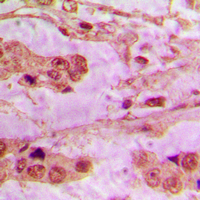

Immunohistochemical analysis of API5 staining in human lung cancer formalin fixed paraffin embedded tissue section. The section was pre-treated using heat mediated antigen retrieval with sodium citrate buffer (pH 6.0). The section was then incubated with the antibody at room temperature and detected using an HRP conjugated compact polymer system. DAB was used as the chromogen. The section was then counterstained with haematoxylin and mounted with DPX.